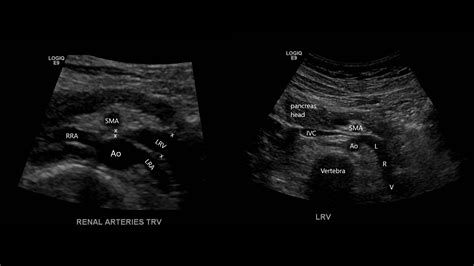

To grasp the mechanical nature of this condition, it is helpful to visualize the anatomy of the abdomen. The left renal vein travels horizontally across the abdomen to deliver blood from the left kidney into the inferior vena cava. In patients with Nutcracker Syndrome, the angle at which the superior mesenteric artery branches off the aorta is unusually narrow. This anatomical narrowing acts like a clamp, compressing the renal vein.

When the vein is compressed, the blood cannot flow freely. This results in high venous pressure, which can cause the vein to become dilated or distended. Furthermore, this back pressure often leads to the development of varicocele (enlarged veins in the scrotum) in men or pelvic congestion syndrome in women. Because this involves structural anatomy, it is a mechanical issue rather than a lifestyle-related disease, which is why it often requires specialized vascular consultation for proper management.

Diagnosing this condition requires advanced imaging techniques to visualize the vascular anatomy and confirm the compression. Doctors typically use a combination of non-invasive and invasive tests to determine the severity of the obstruction.

Doppler Ultrasound Evaluates blood flow velocity and identifies narrowing of the renal vein.